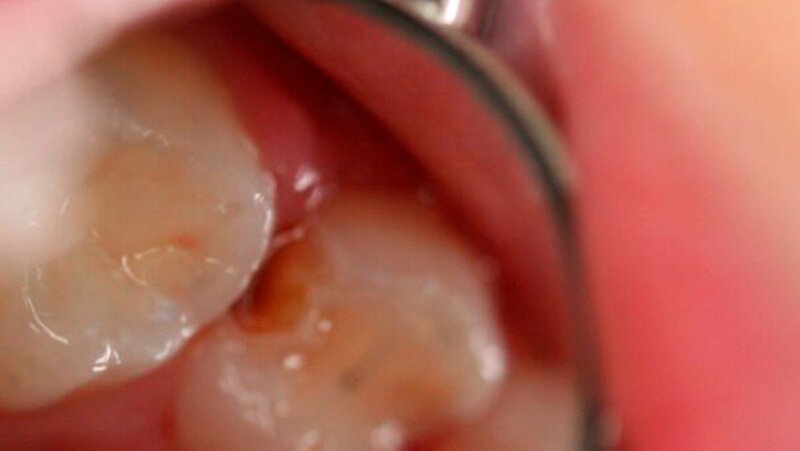

Die klinische Untersuchung des Mundraums zeigte eine gesunde Mundschleimhaut, eine gesunde Zunge und ein vollständiges jedoch kariöses Milchgebiss:

caries media (ICDAS 5) an den Zähnen 64 (okklusale und distale Fläche, Abb. 1a) und 75 (okklusal)

eine insuffiziente Füllung an 84 (okklusale und distale Fläche)

weitere nicht kavitierte Läsionen an 75, 85 und an den Oberkiefer-Frontzähnen (bukkale Fläche; ICDAS 2), die als inaktiv eingestuft wurden.

Alle Approximalflächen wurden mittels der faseroptischen Translumination (FOTI) untersucht, ohne Hinweis auf weitere approximale Dentinläsionen. Röntgenologisch war bei dem Zahn 64 keine pulpale Beteiligung sowie eine Dentinbrücke zwischen der kariösen Läsion und der Pulpa sichtbar (Abb. 1b). Die Schmerzanamnese und die Perkussion für Zahn 64 waren ebenfalls negativ. Zahn 74 zeigt eine periapikale und interradikuläre Radioluzenz, was aufgrund der erkennbaren pulpalen Beteiligung die Hall-Technik explizit ausschließt.